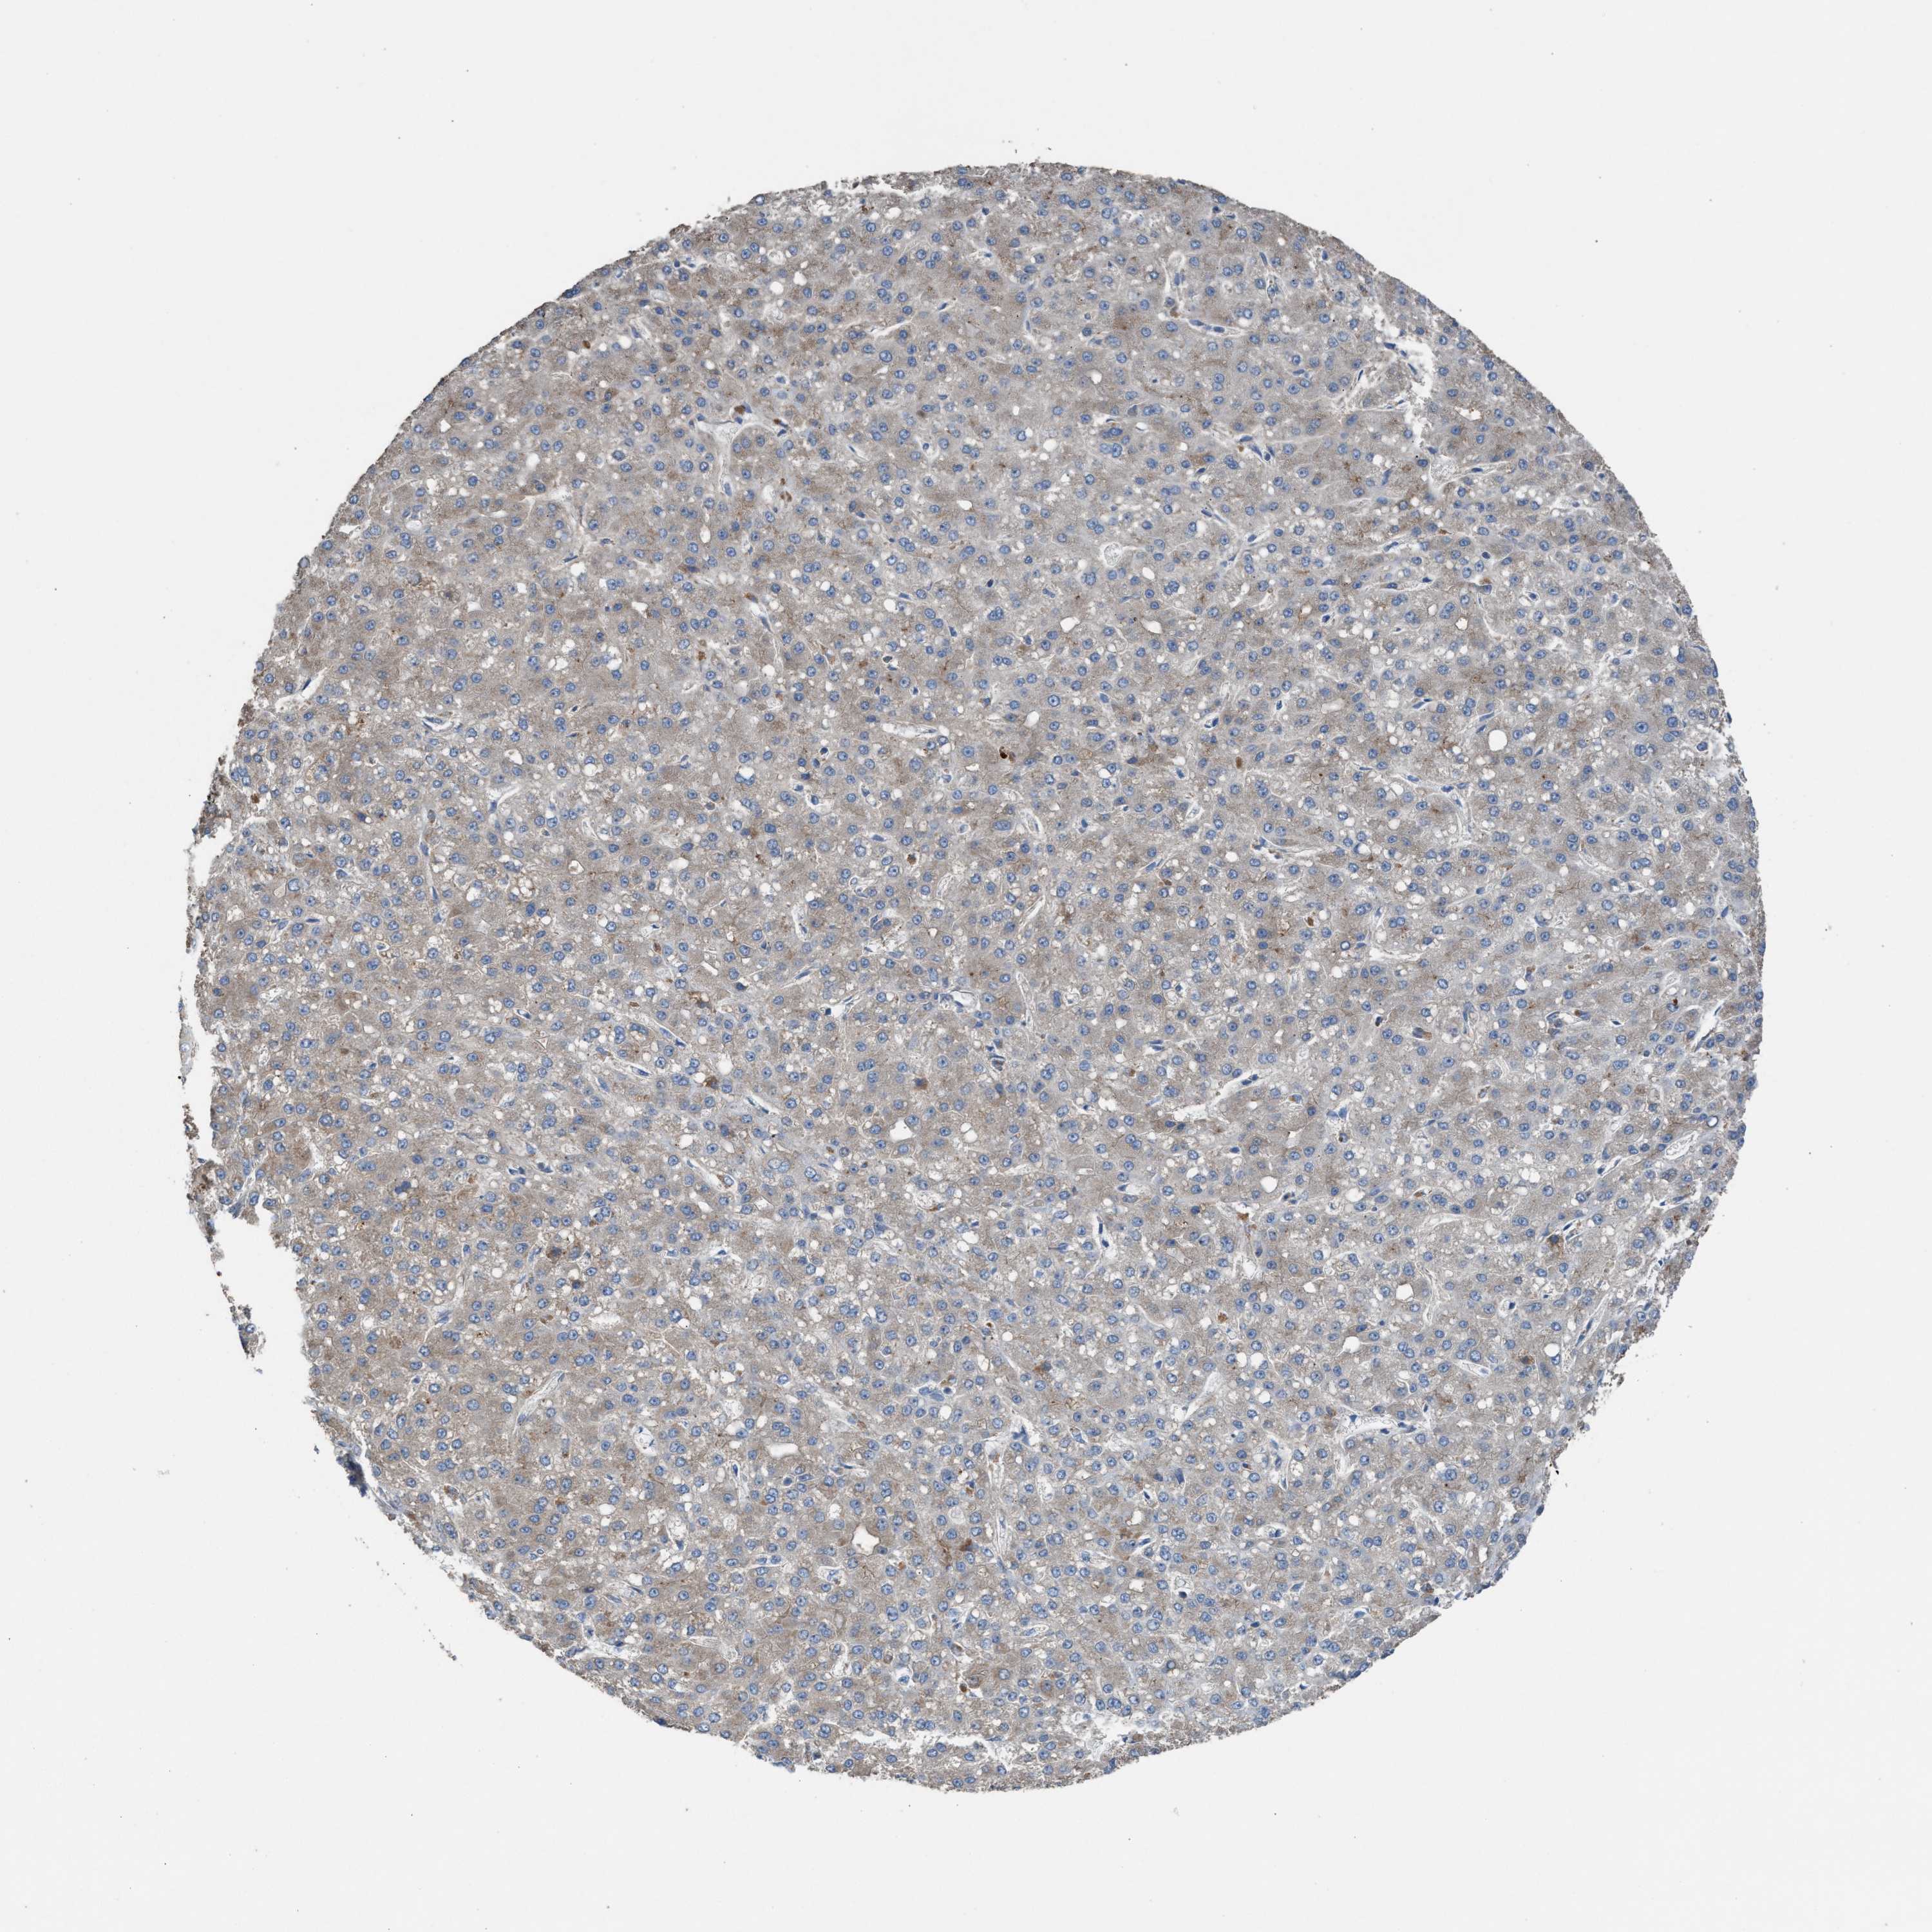

LIVER CANCER - Protein expressioni

A mouse-over function shows sample information and annotation data. Click on an image to view it in a full screen mode. Samples can be filtered based on level of antibody staining by selecting one or several of the following categories: high, medium, low and not detected. The assay and annotation is described here.

Antibody stainingi

Antibody staining in the annotated cell types in the current human tissue is reported as not detected, low, medium, or high, based on conventional immunohistochemistry profiling in selected tissues. This score is based on the combination of the staining intensity and fraction of stained cells.

Each image is clickable and will lead to virtual microscopy that enables deeper exploration of all samples and also displays staining intensity scores, fraction scores and subcellular localization as well as patient and tissue information for each sample.

Antibody HPA021545

Antibody HPA021849

Staining

High

Medium

Low

Not detected

Intensity

Strong

Moderate

Weak

Negative

Quantity

>75%

75%-25%

<25%

None

Location

Nuclear

Cytoplasmic/membranous

Cytoplasmic/membranous,nuclear

Cholangiocarcinoma

Carcinoma, Hepatocellular, NOS